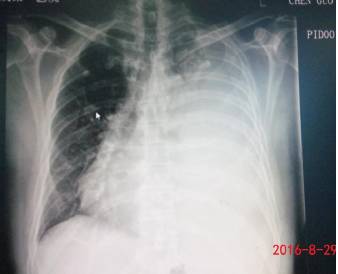

由于查体左侧呼吸音低,叩诊浊音,不排除有胸腔积液可能,急查胸部超声,提示:左侧胸腔积液,中等量以上。同时急查胸片,提示左侧胸腔大量积液。

2016-8-29当晚在B超定位下行左侧胸腔穿刺闭式引流术,当天共引流出淡黄色胸水700ml。患者诉胸闷较前显著减轻。8-29日胸水标本送检结果如下: